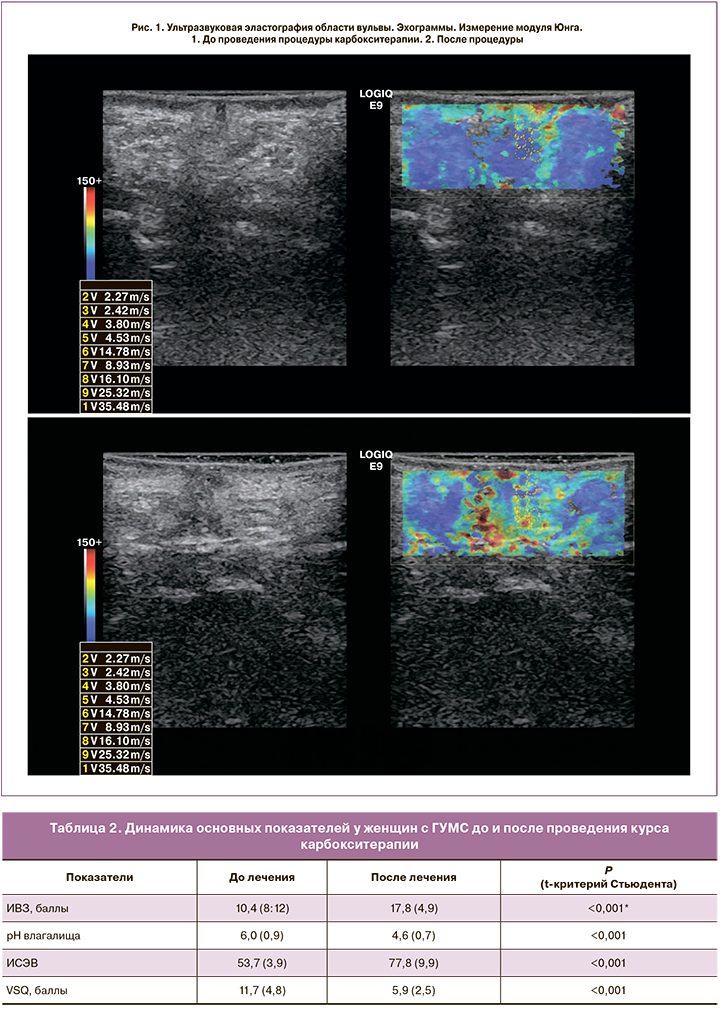

Установлено, что после проведения процедур карбокситерапии под ультразвуковым контролем по всем клиническим, лабораторным, инструментальным показателям получены положительные результаты (табл. 2).

Отмечен рост показателей ИВЗ (17,8 (4,9) по сравнению с исходными данными – 10,4 (8;12)) на 30%, что подтверждается уменьшением атрофических явлений (истончения, трещины слизистой) и увеличением количества влагалищного секрета. Нормализация уровня рН после лечения с 6,0 (0,9) до 4,6 (0,7) (р<0,001) свидетельствует о нормализации кислотно-щелочного баланса.

Согласно полученным данным, ИСЭВ до лечения составлял 53,7 (3,9), после – 77,8 (9,9). При оценке клеточного состава слизистой оболочки замечены признаки восстановления эпителия влагалища: уменьшение базальных, парабазальных, промежуточных и статистически значимое увеличение поверхностных клеток (р<0,001).

При сравнении средних значений баллов опросника VSQ (до лечения – 11,7 (4,8) и после проведения карбокситерапии – 5,9 (2,5)) было установлено, что снижаются частота и интенсивность симптомов ВВА (сухости, зуда, жжения и дискомфорта) почти на 50%, что говорит о высокой эффективности проведенной терапии (p<0,001). Что касается влияния симптомов ВВА на сексуальную сферу, было также отмечено выраженное уменьшение проявлений или полное исчезновение диспареунии.

По результатам данных, приведенных в таблице 4, отмечается изменение жесткости (эластичности) зоны интереса, окрашивания мягких тканей, снижение среднего значения модуля Юнга в зоне интереса сразу после и через 1 месяц проведения процедуры карбокситерапии.

Благодаря ультразвуковому контролю и мониторингу были подтверждены основные физиологические эффекты, характеризующие динамику и определяющие положительный эффект проведения процедуры карбокситерапии (рис. 1, 2):

- изменение эхогенности, эхоструктуры тканей вульвы и влагалища (по результатам применения режима серой шкалы);

- изменение эластичности мягких тканей зоны интереса, вероятнее, за счет усиления газообмена в тканях, иммуномодулирующего эффекта, усиления антиоксидантной защиты клеток, регенеративных свойств и восстановления тканей (см. рис. 1);